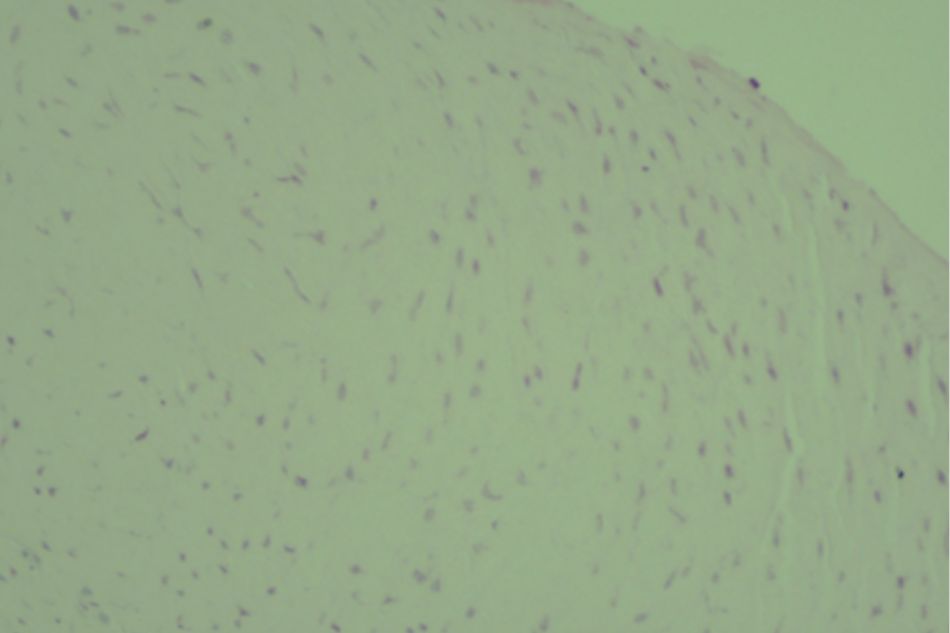

Figure 2.2. Knee joint sample in Group I (rat no.1)

Normal structure of knee joint

Figure 2.3. Knee joint sample in Group I (rat no.2)